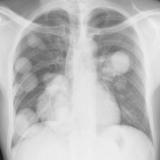

Nodules & Masses

Album: Nodules & Masses

Date: 01/25/2006

Size: 37 items

Views: 58706